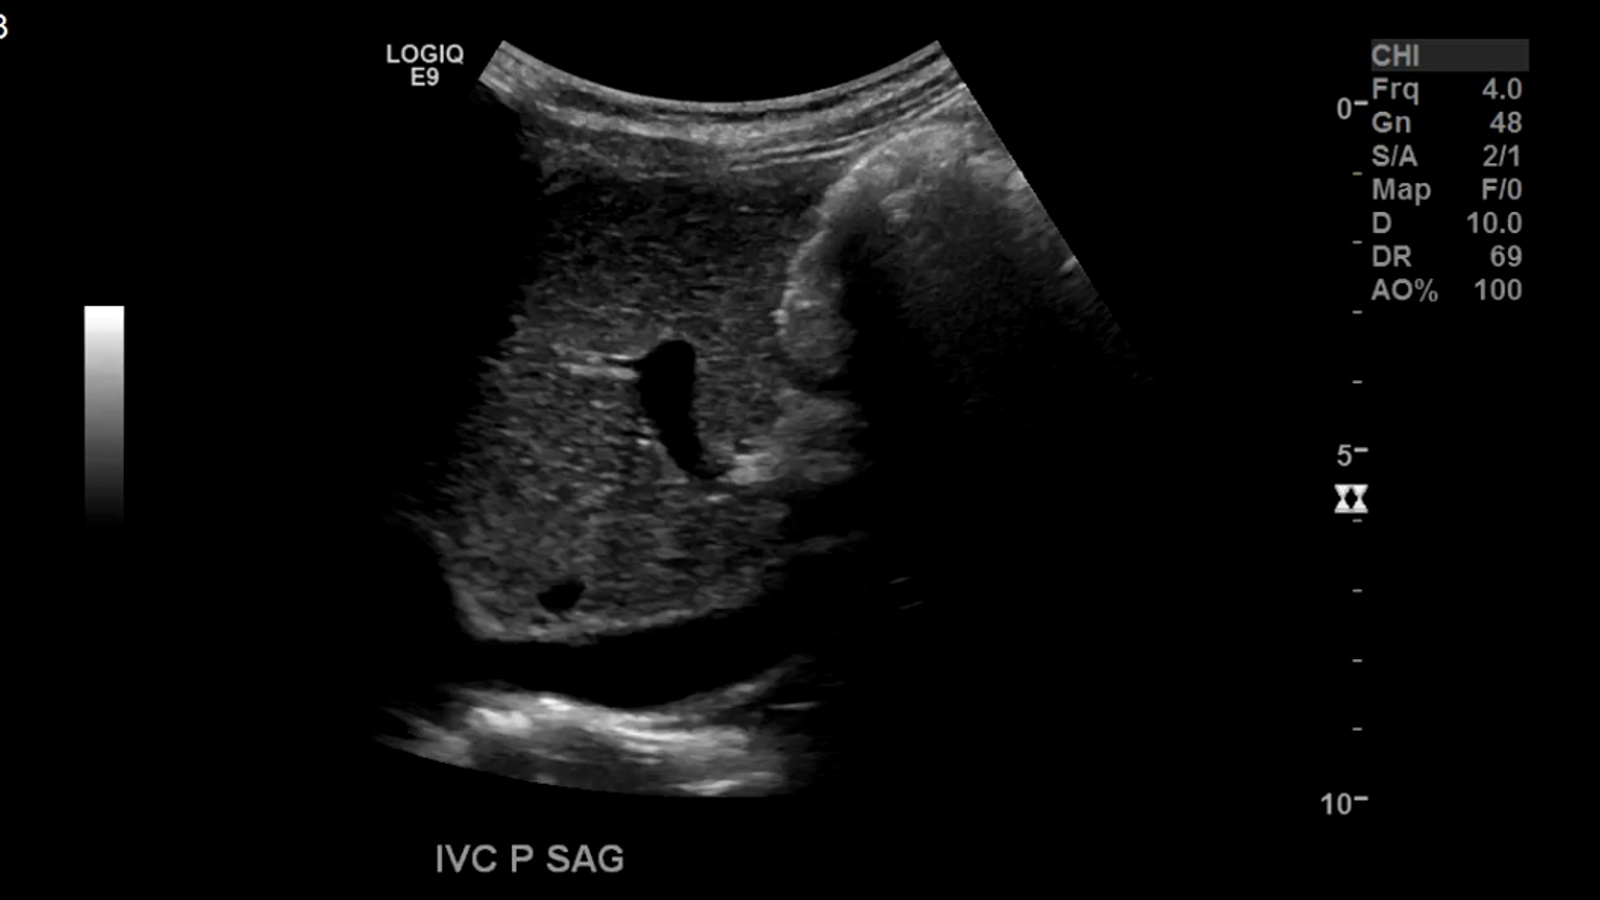

Inferior Vena Cava

The inferior vena cava is the largest abdominal vein receiving deoxygenated blood from the Kidneys, Liver, Spleen and Gastrointestinal system among others.

The renal arteries are paired blood vessels that arise from the mid aorta. The right renal artery is typically longer than the left due to the anatomical location of the aorta being more lateral to left of the body. It courses behind the IVC, which can be used as a window in difficult patients.

As stated before the RRA will be located posterior to the IVC. The LRV will be sandwiched between the Aorta and SMA.